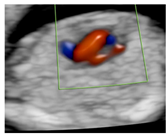

Figure 1.

Case of disagreement in the characterization of color Doppler pattern on the 3VTV between operators 1 and 2 in a case of Ebstein anomaly at 12 + 6 weeks’ gestation. (A,B) show different frames of a videoclip of the 3VTV. (A) Operator 1 observed an abnormal 3VTV pattern in terms of “abnormal vessel number”; (B) operator 2 characterized the same case as with “abnormal vessel dimensions”. AoA, aortich arch; T, trachea; arrow, small pulmonary artery.